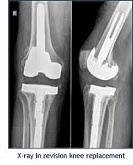

Endoprothetik des Kniegelenks

In den späten Stadien der Arthrose des Knies durch eine ausgeprägte Begrenzung der Bewegung begleitet, konstant starke Schmerzen, körperliche Unversehrtheit Verformung bis zur Genesung der einzige Weg ist der Ersatz des betroffenen Gelenks für eine künstliche - Endoprothetik.

Diese Methode ermöglicht es Ihnen, die richtige Form des Gliedes, eine vollständige Palette von Bewegung im Gelenke, zu entlasten ständige Schmerzen und Knirschen bei Bewegung und als Ergebnis wieder herzustellen, signifikant dem Patienten Lebensqualität zu verbessern.

Im Folgenden sind Röntgenaufnahmen und Fotografien, die die Strecke der Bewegung in der betroffenen Gelenke vor und nach der Operation veranschaulichen.